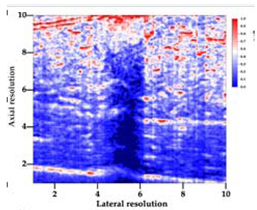

3.5. Echogenicity

| Aerogel Type | US Image | Normalized Intensity Map | 3D Intensity Map | |

| 1 | Muscle |  |  |  |

| 2 | X-silica |  |  |  |

| 3 | X-silica-La2O2S:Eu |  |  |  |

| 4 | SMPU-Mix-14 |  |  |  |

| 5 | SMPU-Mix-18 |  |  |  |

| 6 | BRF-CA |  |  |  |

| 7 | ARF-CA |  |  |  |

| 8 | X-Ca-Alg-2 |  |  |  |

| 9 | X-Ca-Alg-1 |  |  |  |

| Aerogel Type | Imaging Frequency (MHz) | Optimal Frequency (MHz) | Echogenicity | Image Characteristics | Impedance Mismatch (%) | |

| X-silica | 6.5–13.4 | 13.4 MHz | Hypoechoic | Least Hyperechoic | Distinct linear boundary | 92.03 |

| X-silica-La2O2S:Eu | 6.5–13.4 | 13.4 MHz | Hypoechoic | Least Hyperechoic | Distinct linear boundary | 90.28 |

| SMPU-Mix-14 | 6.5–13.4 | 11 MHz | Hyperechoic | Moderately Hyperechoic | Irregular boundary | 98.33 |

| SMPU-Mix-18 | 6.5–13.4 | 11 MHz | Hyperechoic | Moderately Hyperechoic | Irregular boundary | 98.23 |

| BRF-CA | 6.5–13.4 | 13.4 MHz | Hyperechoic | Hyperechoic | Waterfall appearance | 97.16 |

| ARF-CA | 6.5–13.4 | 13.4 MHz | Hyperechoic | Hyperechoic | Waterfall appearance | 97.12 |

| X-Ca-Alg-2 | 6.5–13.4 | 11 MHz | Isoechoic | Strongly Hyperechoic | Irregular boundary | 98.03 |

| X-Ca-Alg-1 | 6.5–13.4 | 11 MHz | Isoechoic | Strongly Hyperechoic | Irregular boundary | 97.97 |